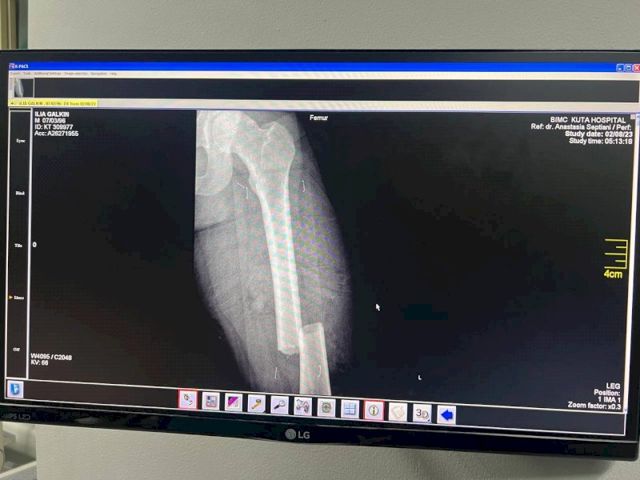

По его словам, сразу после аварии друзья ведущего повезли его в частную больницу. Однако цены там были «сумасшедшие». Тогда Илью отвезли в госпиталь BIMC Kuta. На первичном осмотре выяснилось, что у него множественные переломы и открытый перелом бедренной кости, разорваны мышцы и связки, требуются серьезные операции.

«Первую операцию сделали сегодня, он сейчас в реанимации. Говорят, что состояние стабильное. Операция и нахождение в больнице стоят около 30-50 тыс. долларов. Для нашей семьи это большие деньги, поэтому друзья открыли сбор на лечение. Но волнует и вопрос реабилитации. Либо Илья будет проходить ее там, а это очень дорого, либо его как-то надо транспортировать в Россию», - говорит Павел Галкин.